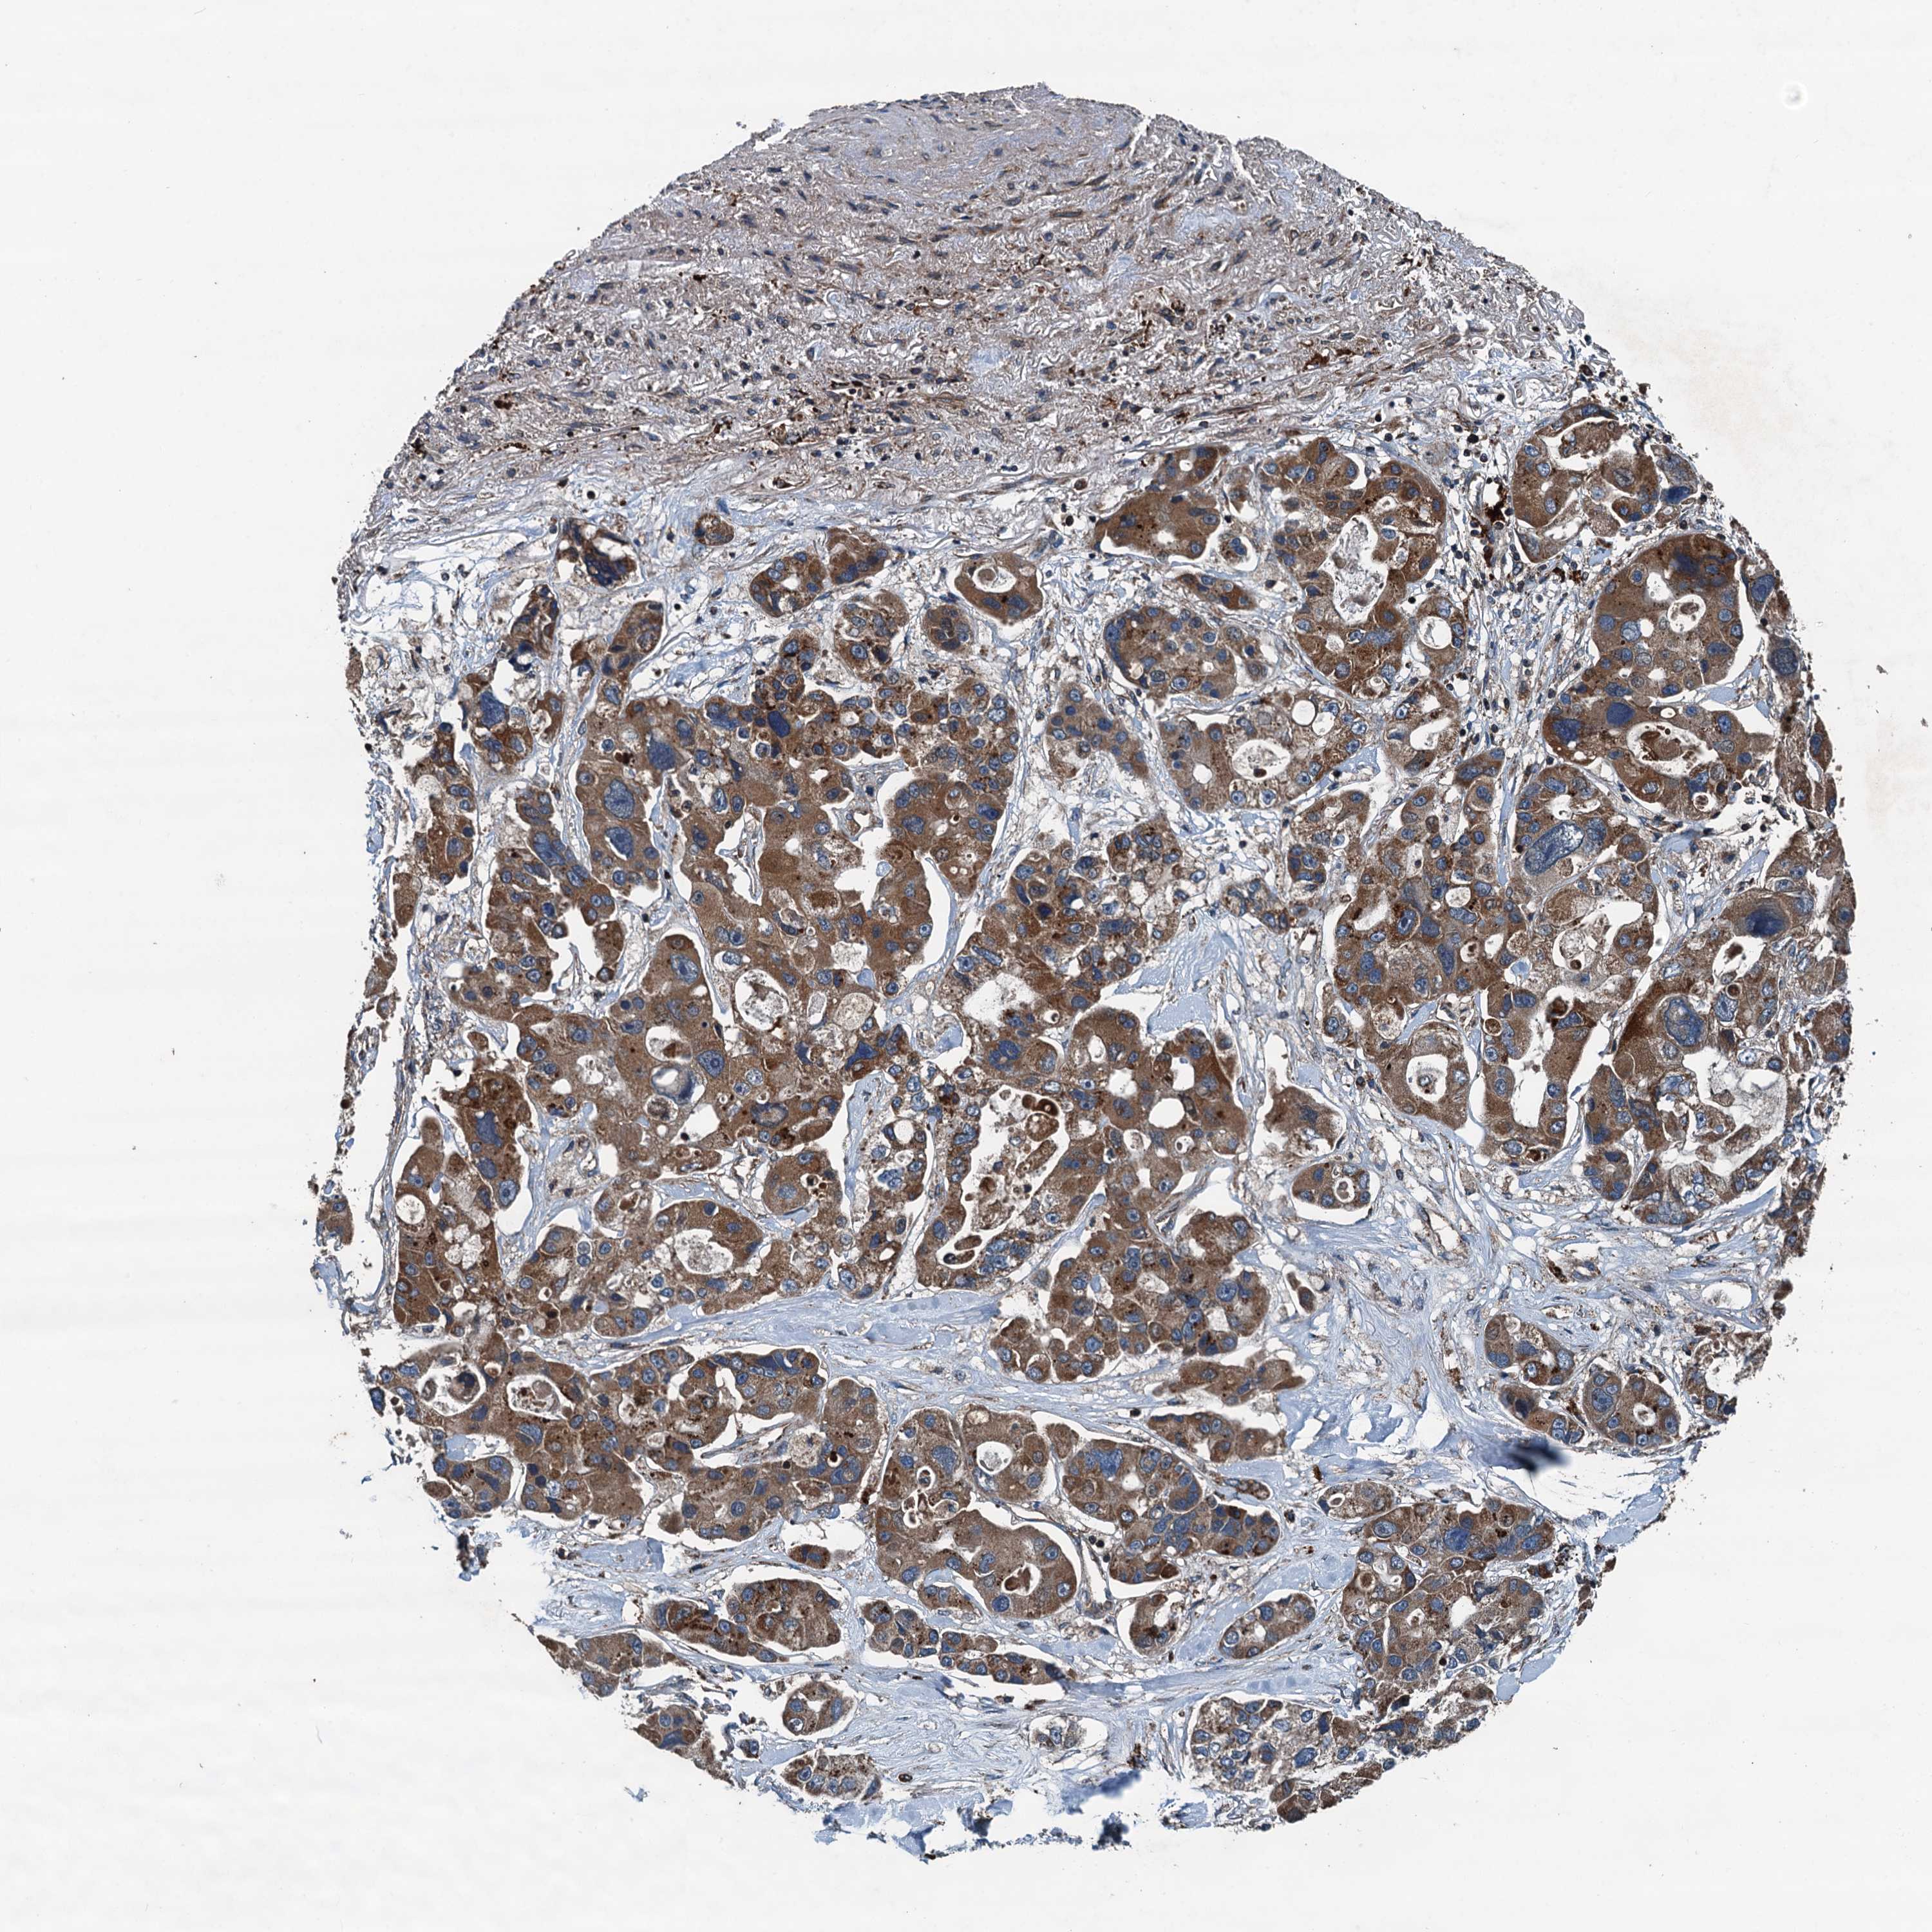

CANCER LUNG CANCER Show tissue menu

Lung cancer

Human cancer

Lung adenocarcinoma